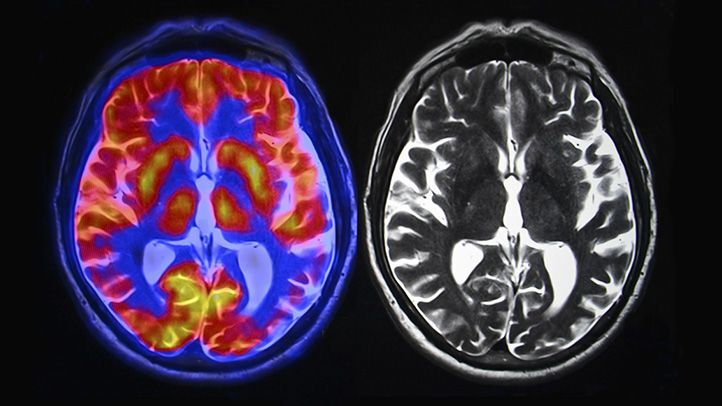

Contrast-enhanced computed tomography (CE-CT) imaging is essential for visualising joint structures in detail and supporting tailored interventions. This project will conduct a comprehensive investigation of both current and previously utilised clinical contrast agents in CE-CT imaging. This will optimise contrast agent selection to improve imaging precision, enhancing treatment planning and revealing soft tissue health more effectively.